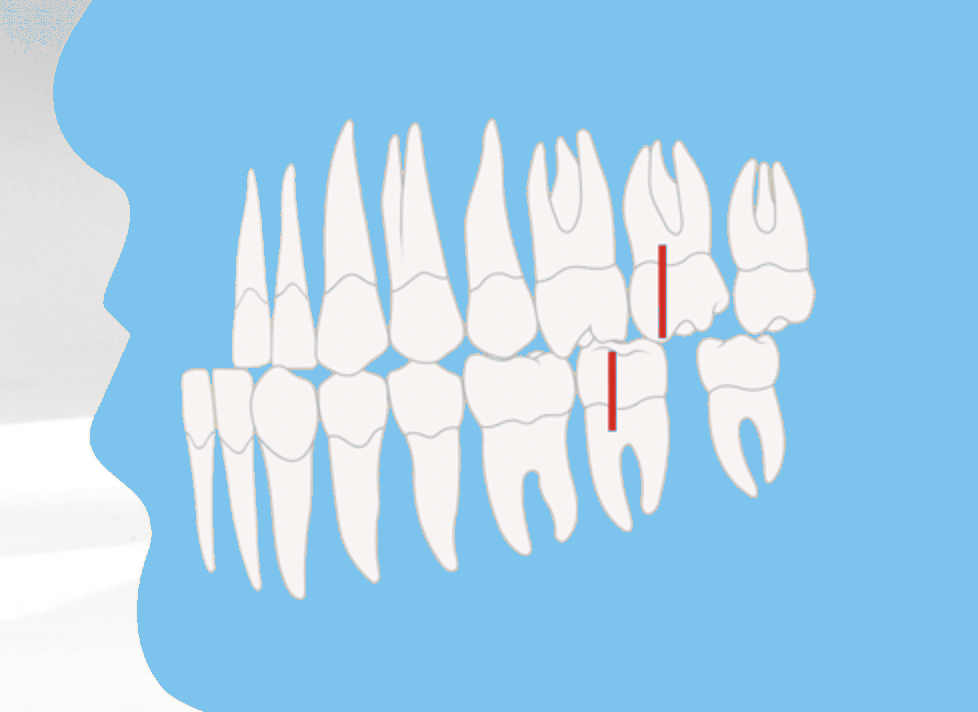

Angle-Klasse III Vorbiss (Mesialbiss / Progenie)

Die Angle-Klasse III beschreibt eine Vorbiss-Fehlstellung, die auch als Mesialbiss oder Progenie bezeichnet wird. Dabei steht der Oberkiefer zu weit zurück bzw. der Unterkiefer zu weit nach vorne.

Charakteristisch ist, dass der vordere Höcker des ersten großen Backenzahns im Oberkiefer hinter den entsprechenden Backenzahn im Unterkiefer beißt. In der Folge liegen die unteren Schneidezähne vor den oberen Schneidezähnen. Dies führt zu funktionellen Einschränkungen beim Abbeißen und Kauen.

- Angle-Klasse III (Mesialbiss): Unterkiefer ist im Verhältnis zu groß oder Oberkiefer zu klein. Typisch bei Progenie (Vorbiss).

Auswirkungen auf das Gesichtsprofil

Neben den funktionalen Problemen wirkt sich die Angle-Klasse III auch stark auf die Gesichtsästhetik aus. Typisch ist ein vorstehendes Kinn, wodurch das Gesicht häufig streng oder „grimmig“ erscheint. Ohne Behandlung können sich die funktionellen Probleme verschlimmern und die Fehlstellung im Erwachsenenalter deutlicher ausgeprägt zeigen.

Infografik: Die Angle-Klassen (I - III)

Angle-Klasse III

Vorbiss / Mesialbiss Unterkiefer zu weit vorne Kinn wirkt vorstehend